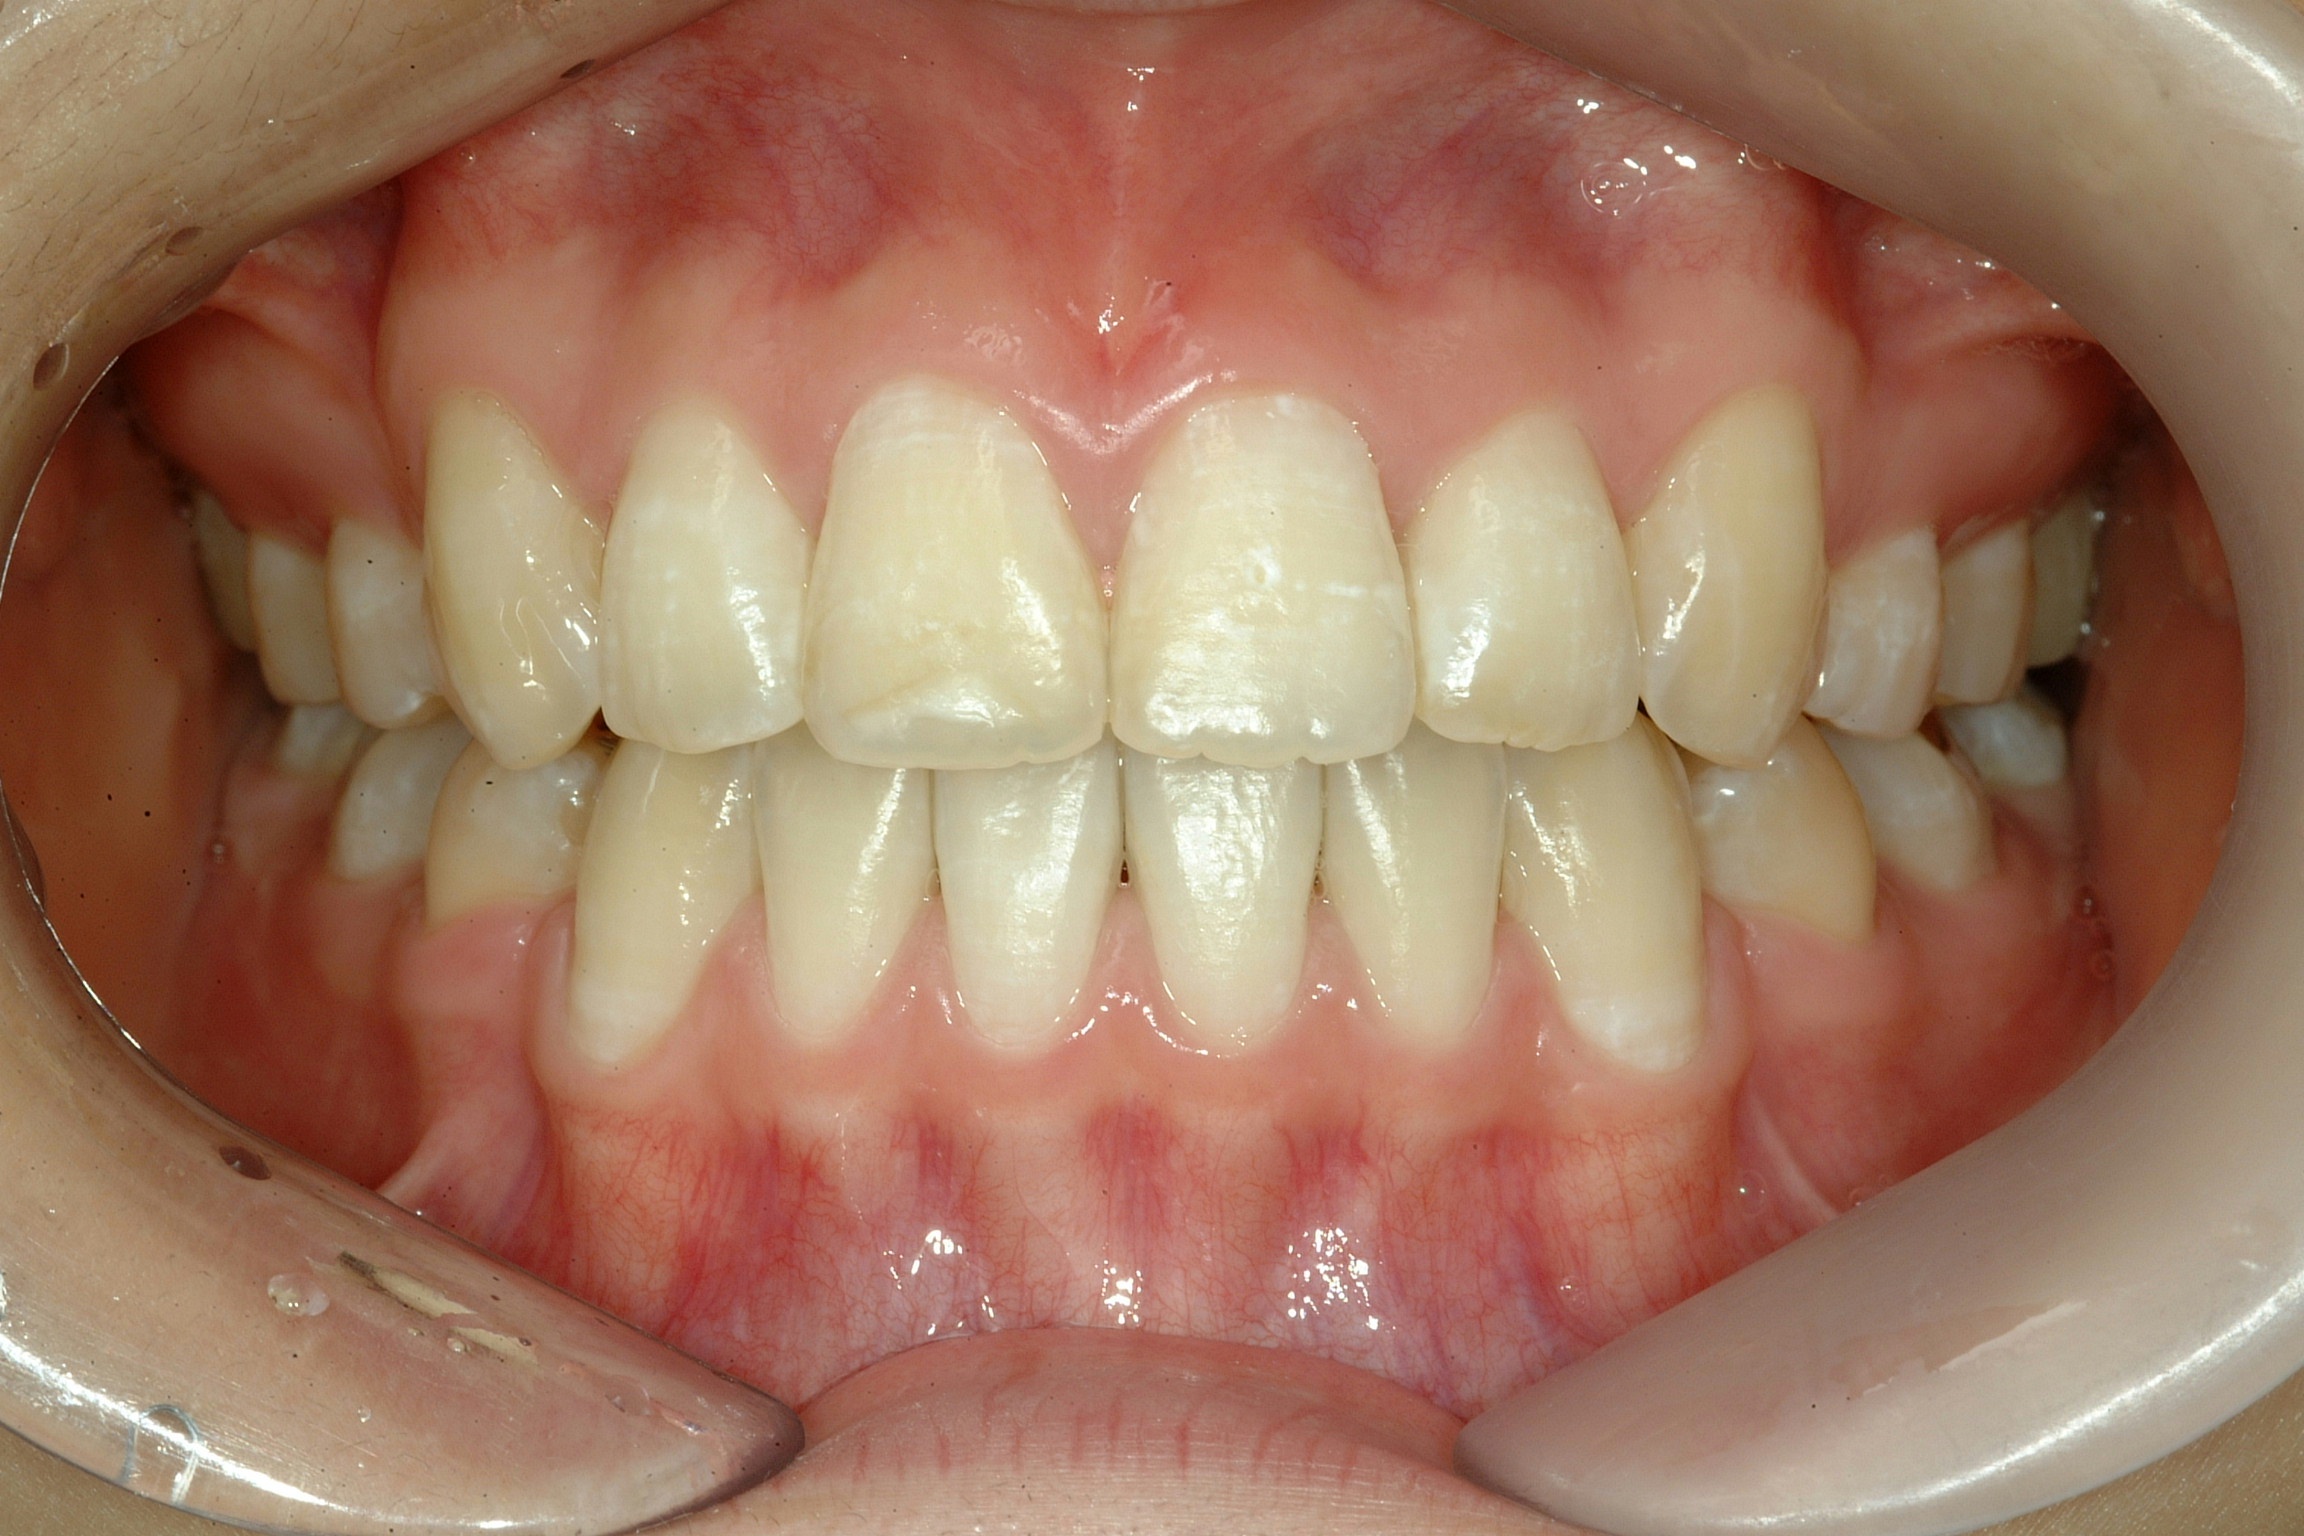

치료 후 사진입니다.